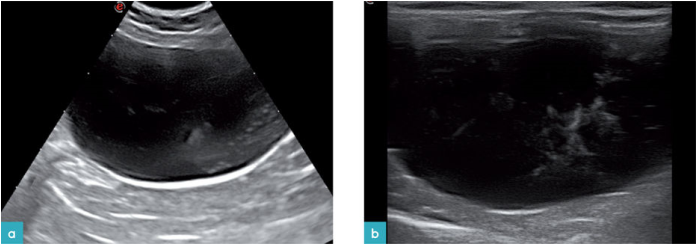

正常的尿液是无回声的,但是旁瓣伪影让膀胱里的尿液变得产回声或看起来像是出现了沉积物。许多猫会出现生理性的脂肪尿,高回声的光点悬浮在尿液中,有时也会见到成团出现的高回声光团(图2)。这些光团不受重力的影响,不产生声影,不产生混响伪影及闪烁伪影。